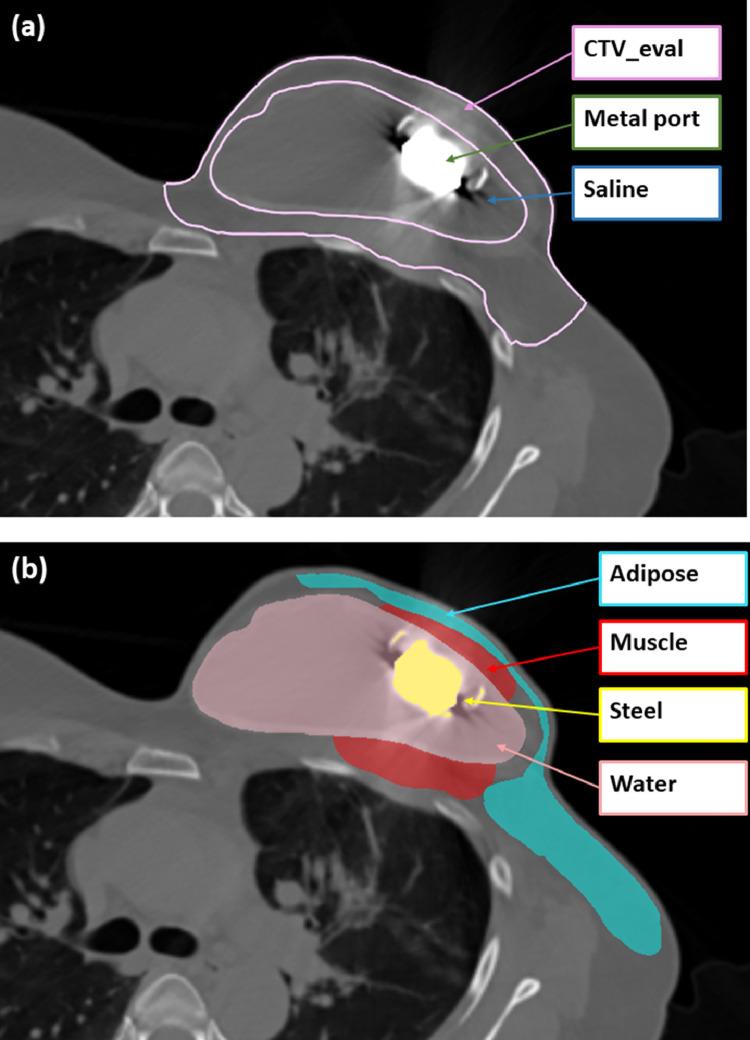

Proton beam therapy can significantly reduce cardiopulmonary radiation exposure compared with photon-based techniques in the postmastectomy setting for locally advanced breast cancer. For patients with metallic port tissue expanders, which are commonly placed in patients undergoing a staged breast reconstruction, dose uncertainties introduced by the high-density material pose challenges for proton therapy. In this report, we describe an intensity modulated proton therapy planning technique for port avoidance through a hybrid single-field optimization/multifield optimization approach.

In this planning technique, 3 beams are utilized. For each beam, no proton spot is placed within or distal to the metal port plus a 5 mm margin. Therefore, precise modeling of the metal port is not required, and various tissue expander manufacturers/models are eligible. The blocked area of 1 beam is dosimetrically covered by 1 or 2 of the remaining beams. Multifield optimization is used in the chest wall target region with blockage of any beam, while single-field optimization is used for remainder of chest wall superior/inferior to the port.